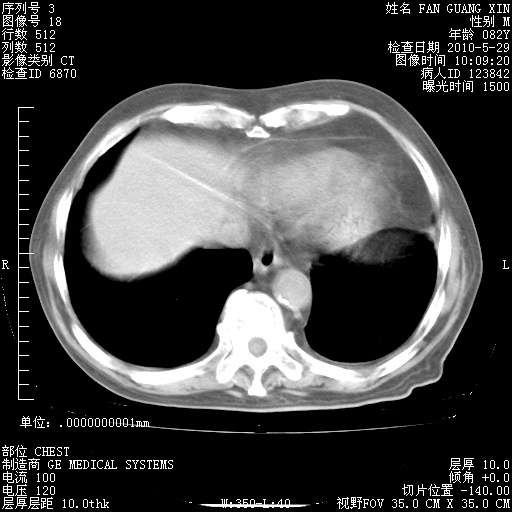

还需要哪些辅助检查?我们医院排除真菌感染没有任何检验方法,胸片好像能够排除肺部真菌感染。

补充:ENA化验全部阴性。免疫五项(IgG、IgA、IgM、C3、C4)只有C4略高。